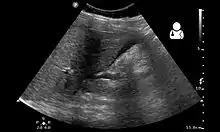

Ultrasound showing a heterotopic pregnancy (intrauterine + extrauterine pregnancies) with signs that the extrauterine (ectopic) pregnancy has ruptured.[1] | |

The gold standard for diagnosing a heterotopic pregnancy is the transvaginal ultrasound. However, the sensitivity of the transvaginal ultrasound for diagnosing a heterotopic pregnancy has been found to range from 26.3% to 92.4%.[5] Therefore, both clinical symptoms and ultrasound imaging are used to make the diagnosis.